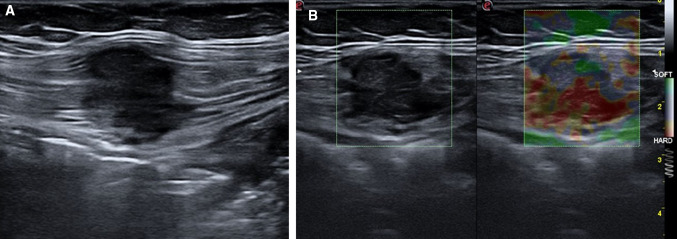

Fig. 15.

Lipoma. Ultrasound shows an oval, isoechoic mass (a) with its greatest diameter parallel to the skin; it is not hypervascularized (b) on color Doppler imaging

Fig. 16.

Desmoid tumor. Ultrasound shows an oval, poorly defined, solid, nonencapsulated mass (a) with internal vascularity (b, c)

Fig. 17.

Neurofibroma. Ultrasound shows an oval, hypoechoic mass with well-defined margins (a) and internal vascularity (b)

Usually, they present as an oval ipoechoic compressible mass (Fig. 15a) with its greatest diameter parallel to the skin, containing short linear reflective striations that run parallel to the skin. Lipomas are usually not hypervascularized at color (Fig. 15b) or power Doppler imaging [92].

On ultrasound, desmoids frequently appear as oval, poorly or well-defined solid soft tissue masses with variable echogenicity (Fig. 16a) that are nonencapsulated and can infiltrate the surrounding tissue, generally abdominal wall muscles. They may present internal vascularity (Fig. 16b, c) and, characteristically, do not cross the midline [97].

Neurofibromas are round, oval or fusiform, and hypoechoic with well-defined margins, and internal cystic changes may be observed (Fig. 17). The most important criterion for the ultrasound diagnosis is the relation of the mass to a nerve [99].